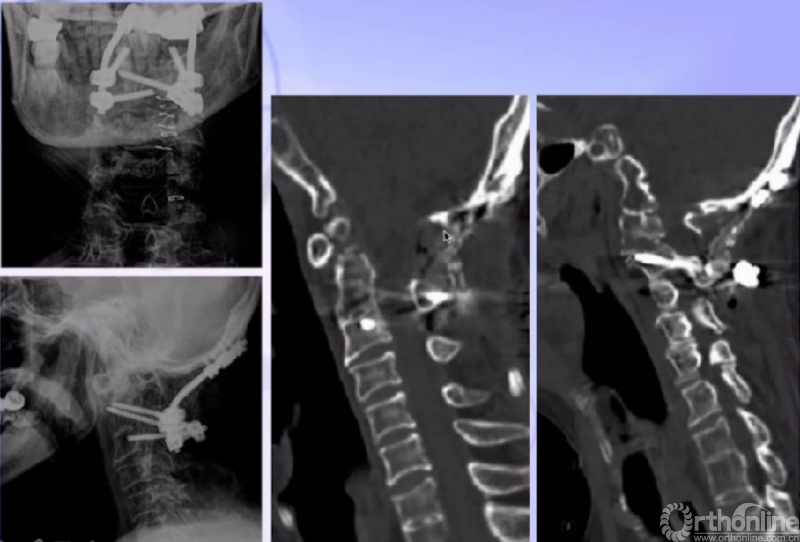

X线正、侧位

CT

术后CT